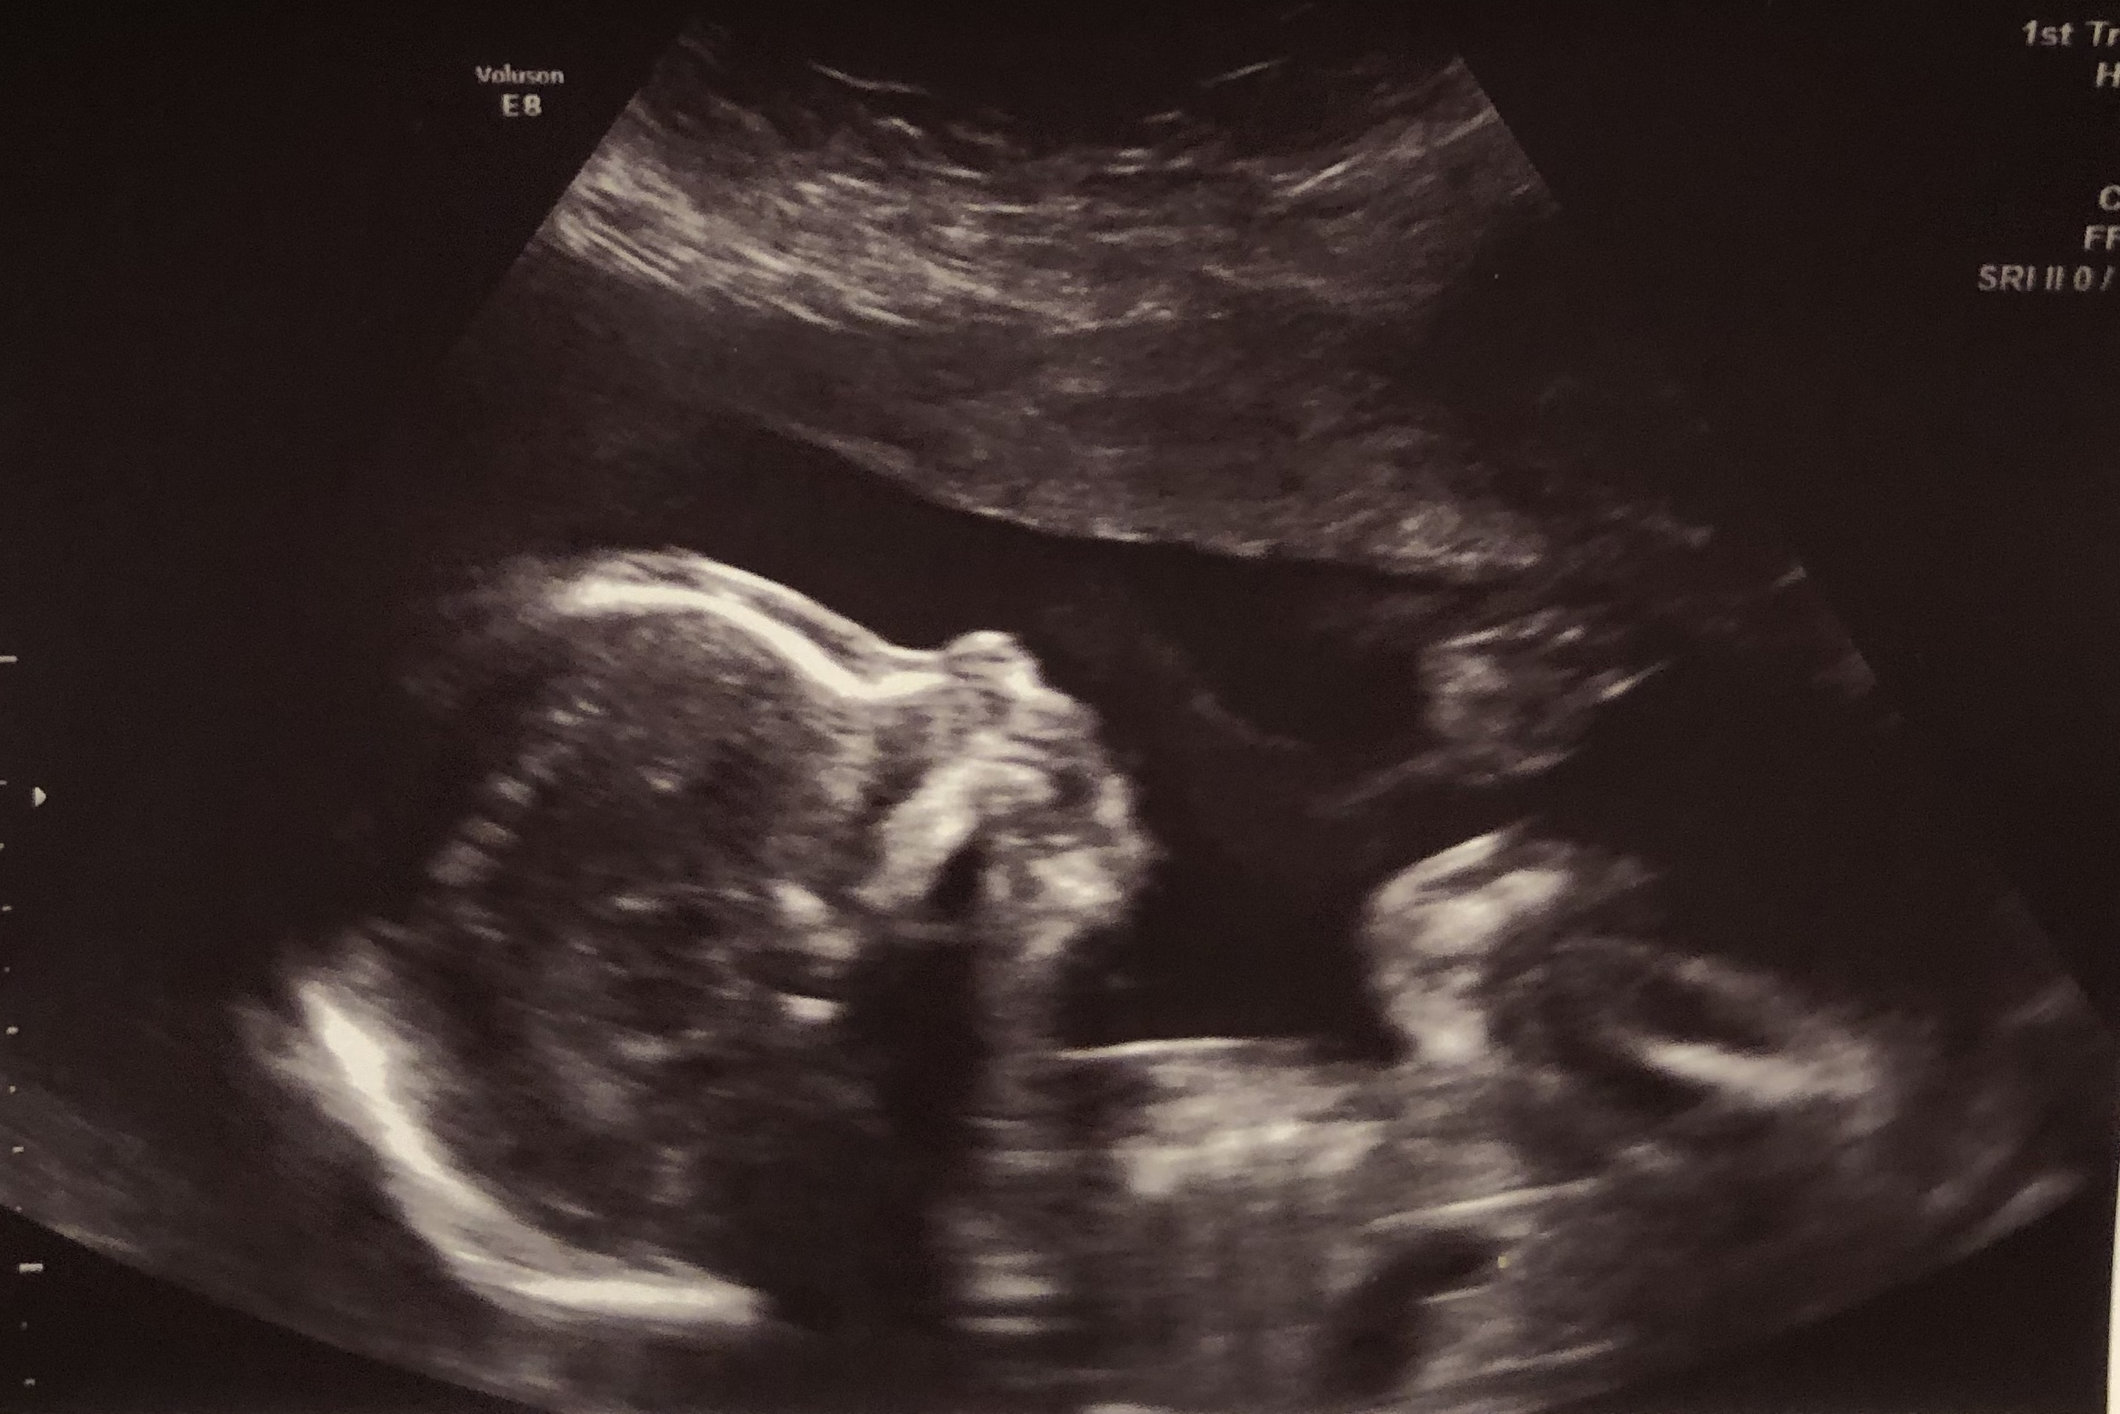

Today was my NT ultrasound; Baby is developing well 12w/5d. Bad news: I have placenta previa (placenta is by the cervix). Doctor said, since uterus is still growing it can still move up. For now my poor DH cant have sexy time with me until my next ultrasound to see if it moved.

Baby G2 is still cooking. Anatomy scan today and everything turned out great. DS came with us and near the end when the tech turned it to 3D mode, he kept calling the baby a monkey and making monkey noises... 🐒

this baby looks a lot like DS did too. Which leads me to think this one is a boy. I’d love to be a boy mom but we’ll have to wait a bit longer to find out!